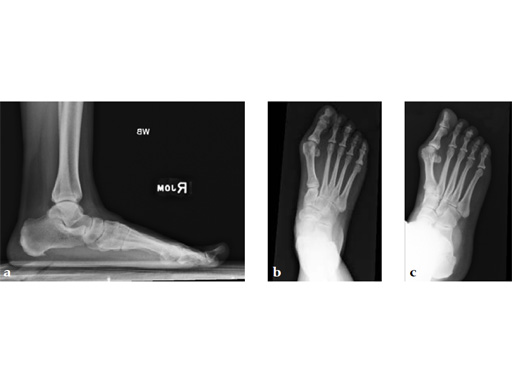

A 48-year-old woman, with hallus valgus and hypermobile medial column, also resulting in pes plano abductovalgus (flatfoot).

Case provided by Andrew Sands, New York, New York, USA

Surgery consisted of first TMT and intertarsal corrective osteotomy plus fusion with movement of the first MT lateral and plantar. This corrects the hallus valgus as well as the PPAV (and stabilizes the medial column).